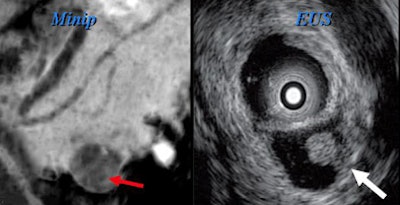

"There's no way to distinguish them, so by the time your cyst has exceeded 4 cm, you've pretty much bought yourself a needle aspiration," Jeffrey said. Esophageal EUS-guided fine-needle aspiration is the key to differentiating these small cyst types and in fact the way to evaluate most lesions larger than 3 cm in diameter.

"If they're greater than 3 cm, we're going to want to go on to needle aspiration, but when they're small -- and particularly if we can identify distinctive morphological features -- we can be very comfortable following these with imaging [MDCT, EUS, or magnetic resonance cholangiopancreatography (MRCP)]," he said. "Cystic cancers are rare, but they invariably have solid components or increase [in size] over time."

Researchers have also experimented with ethanol ablation under EUS guidance for cysts 1 cm and smaller, Jeffrey said of a pilot study from Massachusetts General Hospital in Boston. Gan et al found that in eight of 23 (35%) patients with complete follow-up, the cysts resolved completely, with evidence of epithelial ablation in five other patients who underwent surgical resection (Gastrointestinal Endoscopy, May 2005, Vol. 61:6, pp. 746-752).